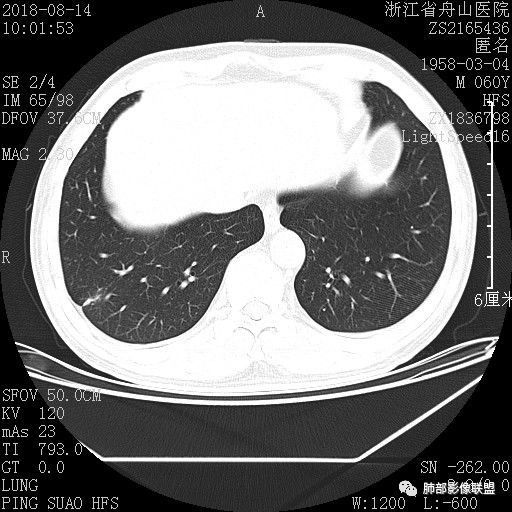

以下是抗真菌后复查结果。6个月后基本吸收。

肺隐球菌感染既往见于有免疫力缺陷病人,比如HIV感染、长期使用激素患者。近年来,随着CT检查的广泛使用,越来越多无免疫力缺陷的肺隐球菌患者被发现。影像学上表现为结节型者约占到三四成。而这种结节在CT诊断上常被当成肺癌而手术,从而造成患者不必要的损害。 医学百科网 | YxBaike.Com

对于急性期的结节,常因病灶多发、病灶边缘模糊,诊断不难;当病灶演变成肉芽肿期时,与肿瘤鉴别相当困难(主要是病灶在随访过程中可以有和肿瘤一样的倍增时间),所以要引起临床足够的重视。 医学百科网 | YxBaike.Com